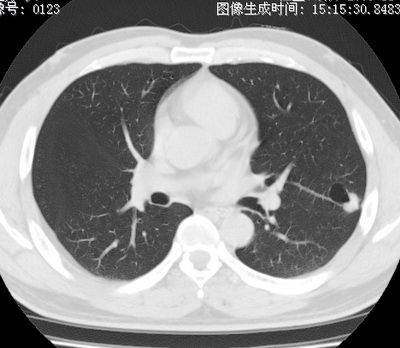

以下是引用zhao_bin2008在2010-1-4 20:15:00的发言:[br]先天性肺囊肿或小的肺隔离症?

以下是引用卜一在2010-1-4 22:09:00的发言:[br]先天性肺囊肿或小的肺隔离症?支持!

以下是引用zsl6918在2010-1-5 5:23:00的发言:[br]良性改变!肺囊肿,先天性支气管闭锁,血管畸形等均有可能。

以下是引用影像之路在2010-1-6 11:10:00的发言:[br]腺癌,最终的病检有些出乎意料之外,术前同志们大多考虑为肺囊肿或小的肺隔离征 [br]回过头来看 小结节呈分叶状,其内侧有一条较粗的静脉供血或许能成为支持诊断腺癌的理由